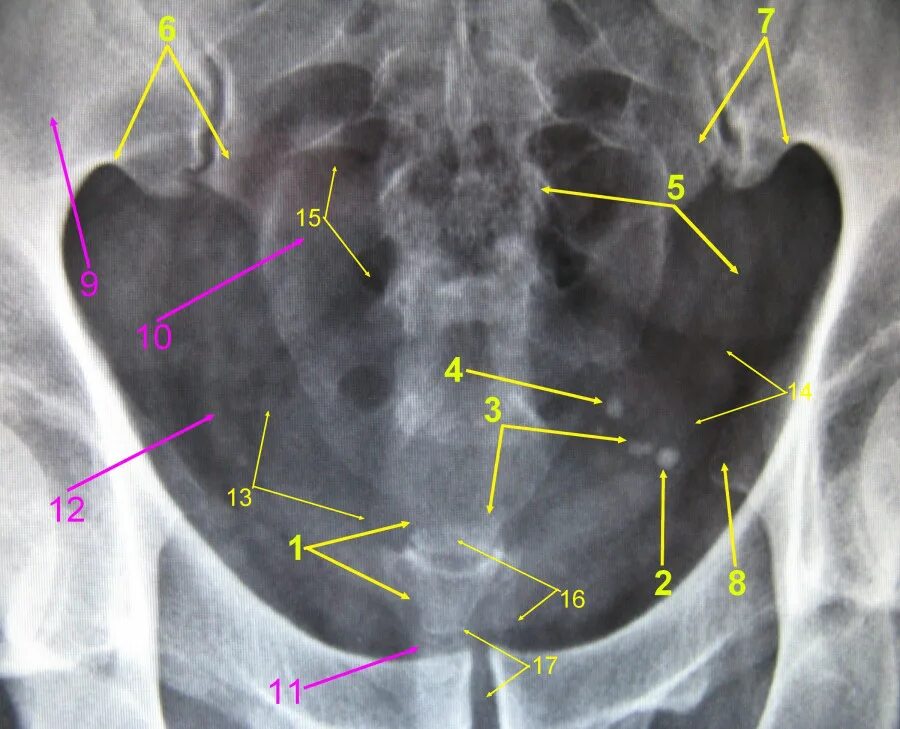

Снимок копчика